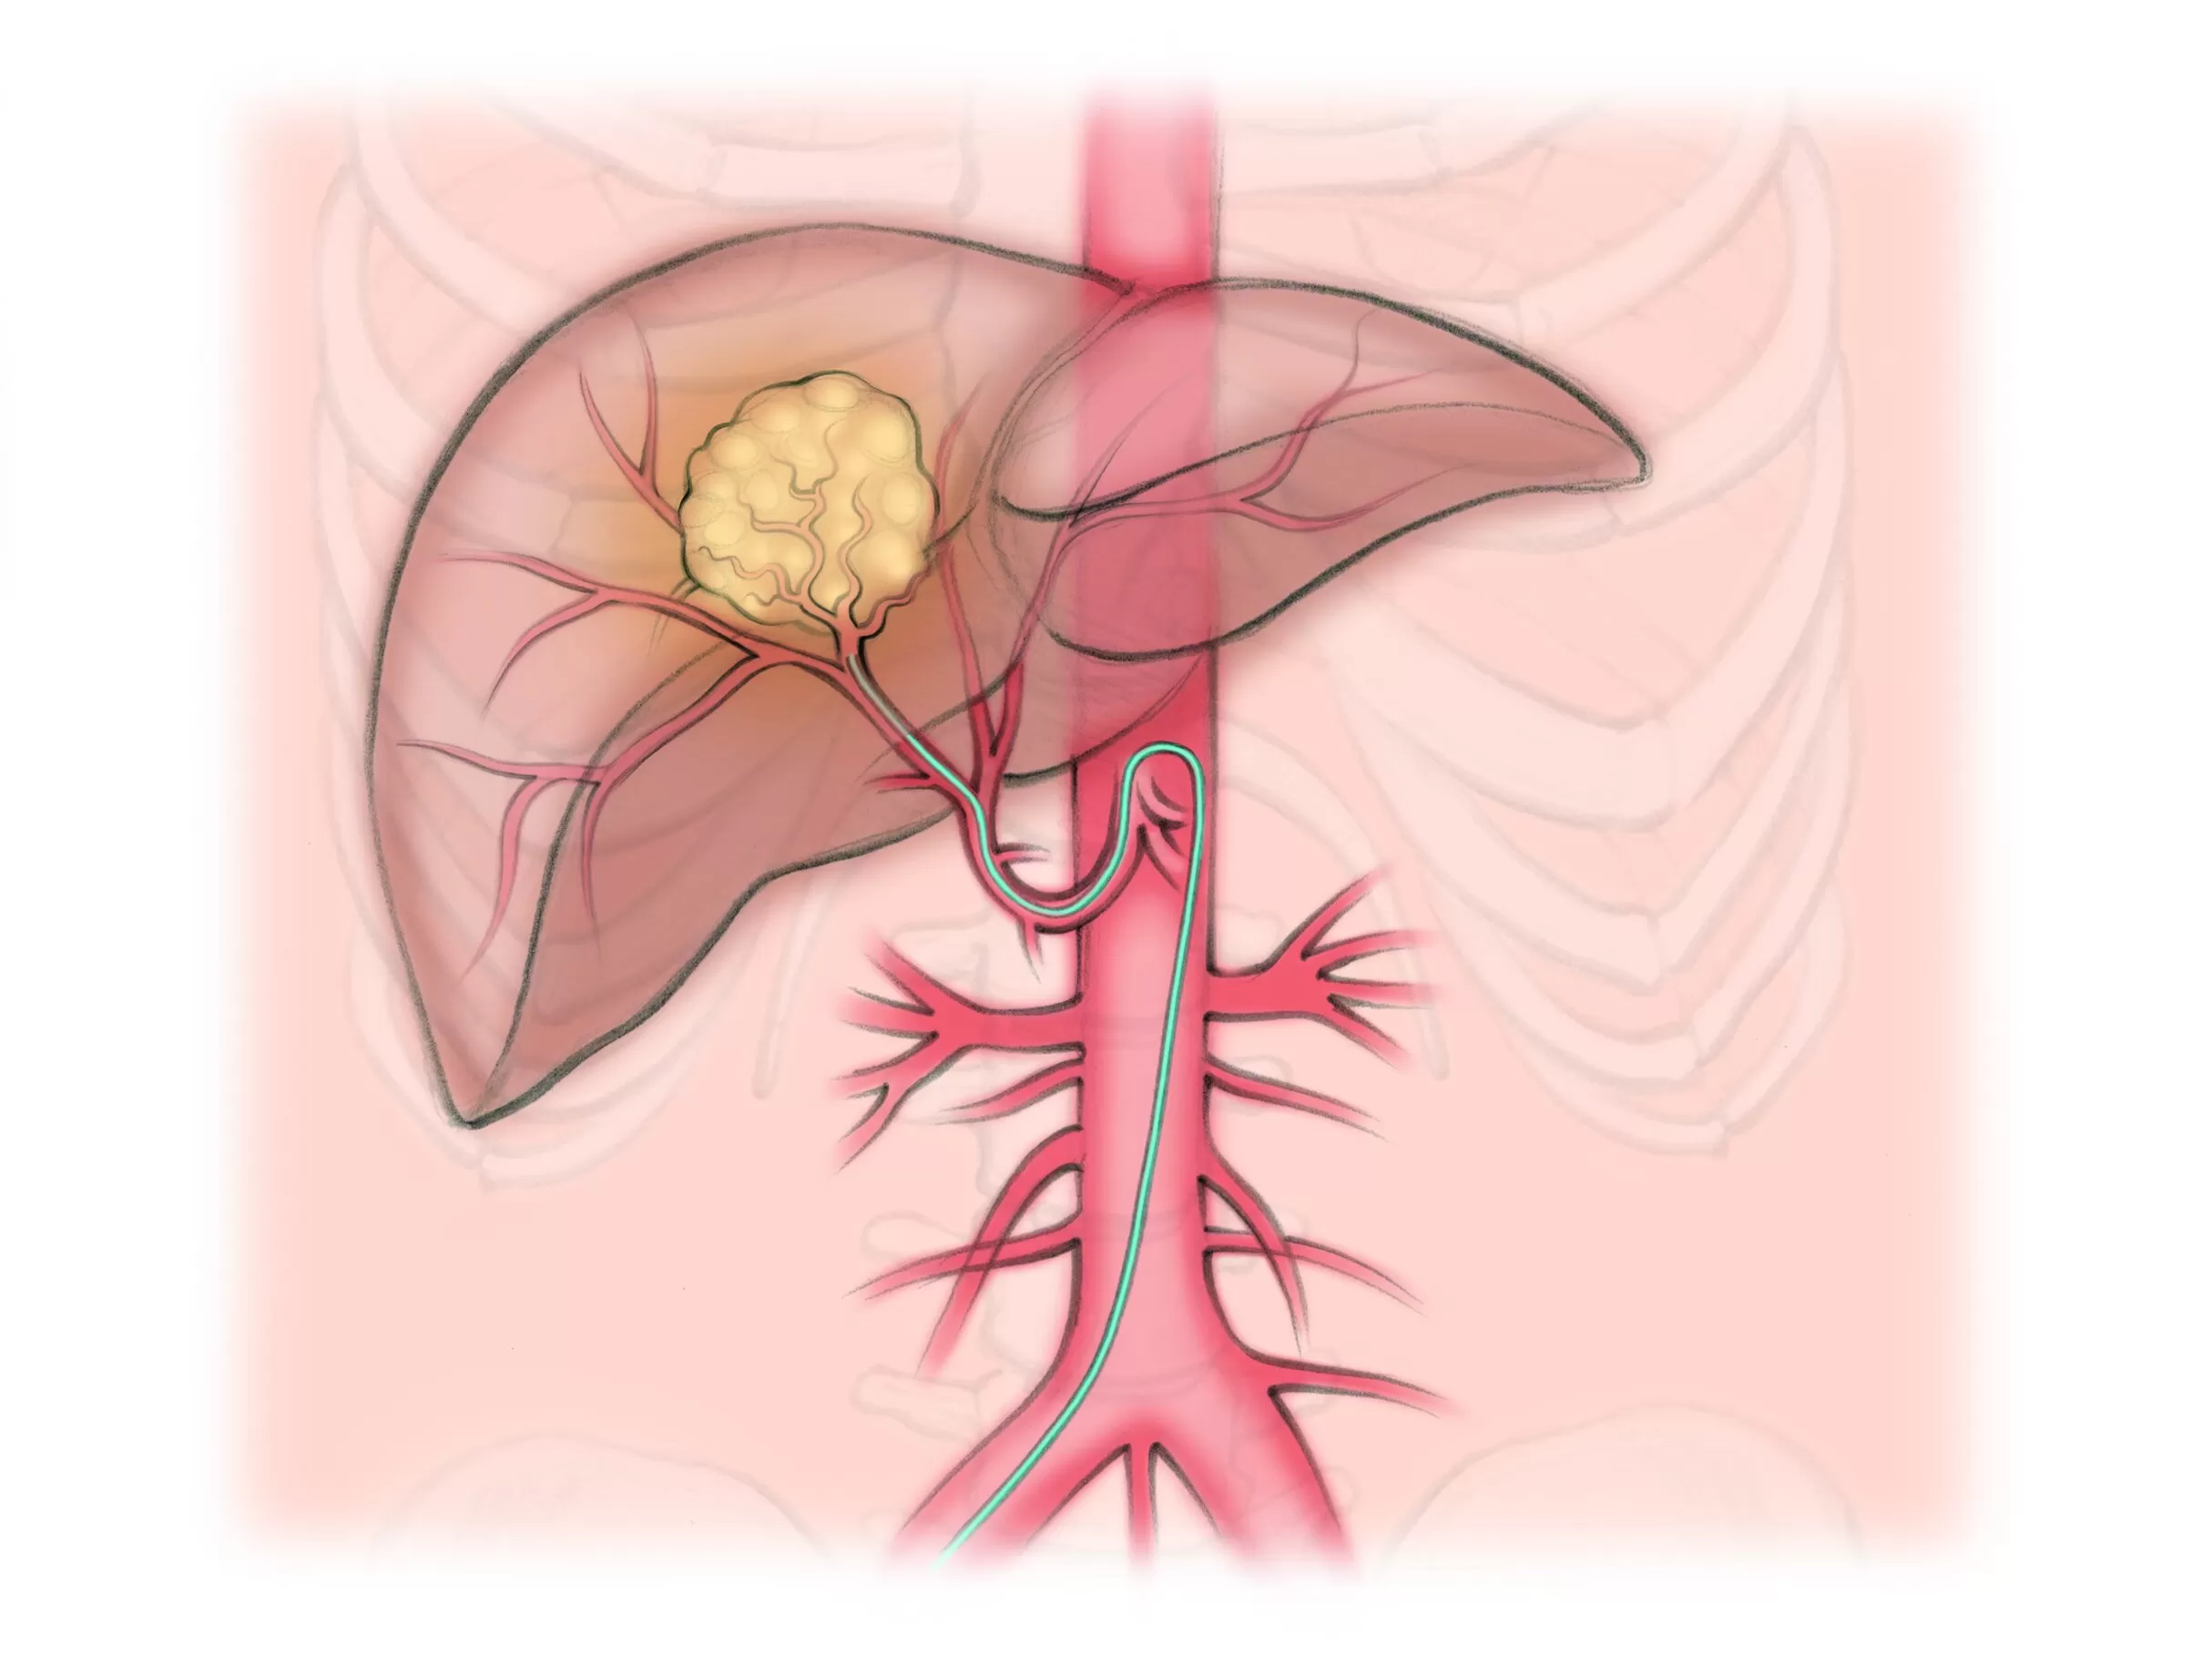

Cancer Treatments

Thanks to remarkable advances in imaging and device technology, we can now reach diseased areas in the body through a tiny needle puncture, and deliver highly targeted treatments with precision, while preserving surrounding healthy tissues. This means less pain, faster recovery, and fewer complications compared to conventional surgery.